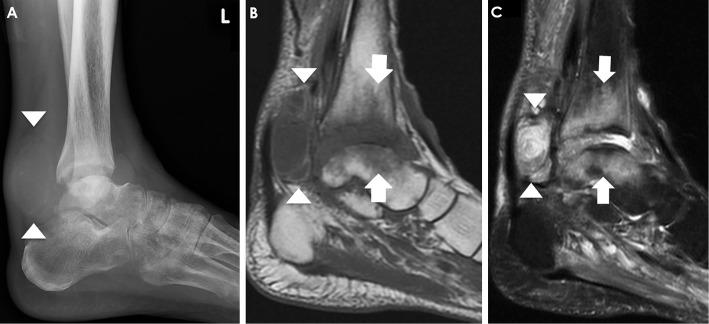

Localized Listeria infection predominantly occurs in the prosthetic and hip joints. We herein report a case of Listeria monocytogenes ankle osteomyelitis in a 73-year-old man receiving adalimumab who was transferred to our hospital because of suspected rheumatoid arthritis (RA) flare. He reported a four-month history of left ankle swelling. A surgical biopsy revealed L. monocytogenes osteomyelitis in the left tibia and talus bones. The patient was successfully treated with antibiotics and surgical debridement. Thus, infection due to L. monocytogenes can present as ankle osteomyelitis in immunocompromised patients and may mimic an RA flare.

局部李斯特菌感染主要发生在假体和髋关节。我们在此报告一例接受阿达木单抗治疗的 73 岁男性的李斯特菌单核细胞增生症性踝关节骨髓炎病例,因疑似类风湿关节炎(RA)发作而转至我院。他报告说,左侧踝关节肿胀已有四个月。手术活检显示左胫骨和距骨有李斯特菌单核细胞增生症性骨髓炎。患者经抗生素和手术清创治疗后痊愈。因此,免疫功能低下患者的李斯特菌感染可表现为踝关节骨髓炎,并可能类似于 RA 发作。